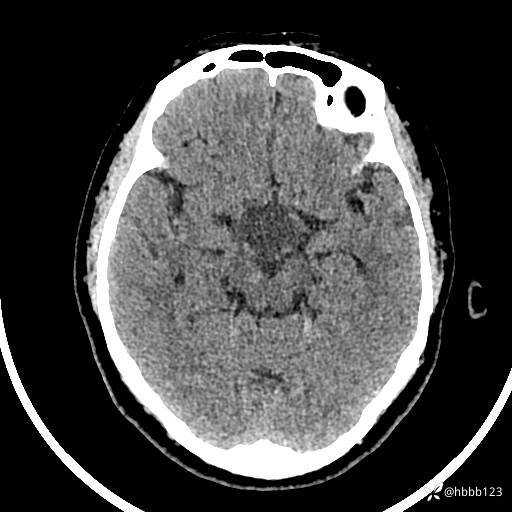

颅脑CT平扫: